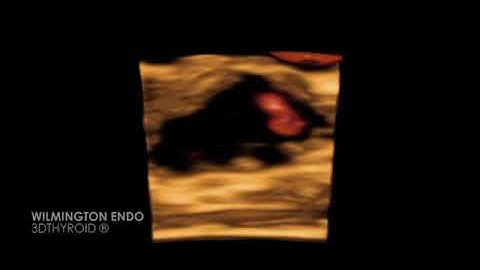

TI-RADS Thyroid Imaging Reporting and Data System Webinar Part III